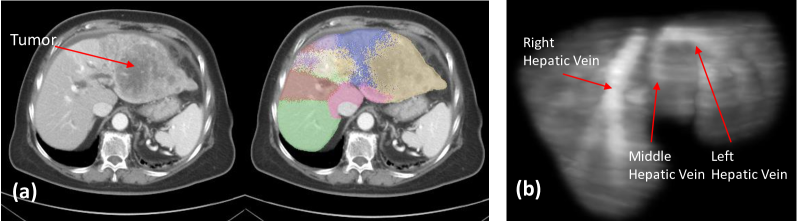

The proposed method does not need explicit vessel priors, unlike [28]. Moreover, as shown in Fig. 6 (b), it can learn anatomical liver landmarks in the graph . However, the proposed method cannot accurately discriminate segments in the liver when a large tumor appears, as shown in Fig. 6 (a). Here, the partial anatomical landmarks in the CT image are absent, such as the left hepatic vein and the left portal vein. To conclude, we propose a D point-based method for Couinaud segmentation for CT images. Our model incorporates implicitly anatomical information, by learning affinities between voxels in the CT volume in a dynamic graph reasoning module. This implicit anatomical information makes our model competitive compared to prior point-based methods, where we exceed PointNet, PointNet, AGCNN and Zhang et al. ’s [28] method on the MSD and LiTS public benchmarks. This approach avoids the time-consuming definition of the prior vessel structure in the liver, while still showing competitive performance.